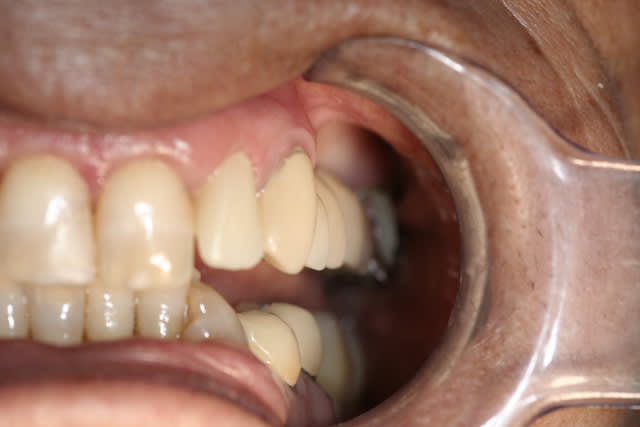

sur la photo "maquillage" on voit que le bord du provisoire a été un peu envahissant sur la canine, avec le bridge définitif la gencive est revenu a sa place, avec des bords foireux la gencive ne revient pas